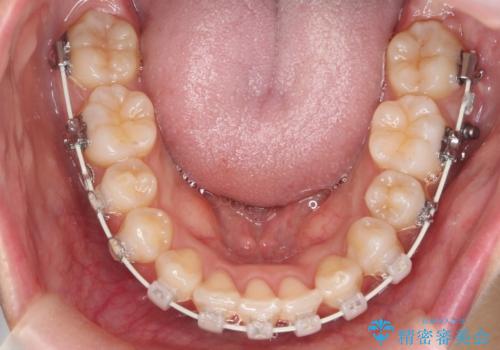

- 矯正装置

- ワイヤー矯正

- 出っ歯を主訴に来院。

上下のかみ合わせが1本分左右ともずれていました。

①上下左右合計4本抜歯(口元は一番下がるプラン、上の奥歯をさらに後ろに下げる必要があるため②より時間がかかる、上下正中は合う)

②上の歯を2本抜歯、下の歯は前歯1本と最小限の抜歯(矯正治療は早く終わる、口元は下がる、抜歯は3本、上下の正中は合わない)

を提示し、

②を選択されました。